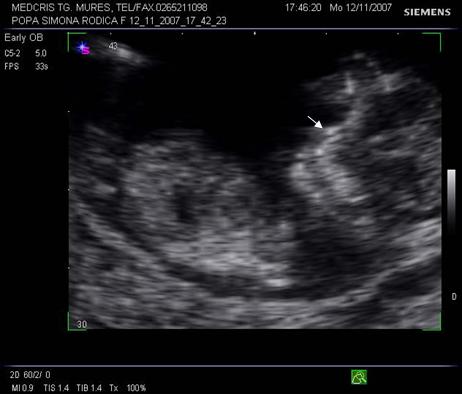

Fig. nr.128 Pliu nuchal cu dimensiunea de 2,9 mm.Cu sageata se remarca alaturat amniosul, magnificatia redusa nu permite obtinerea unei imagini optimale a translucentei nuchale.

Fig. nr.129 Masurarea pliului nuchal la o marire corespunzatoare